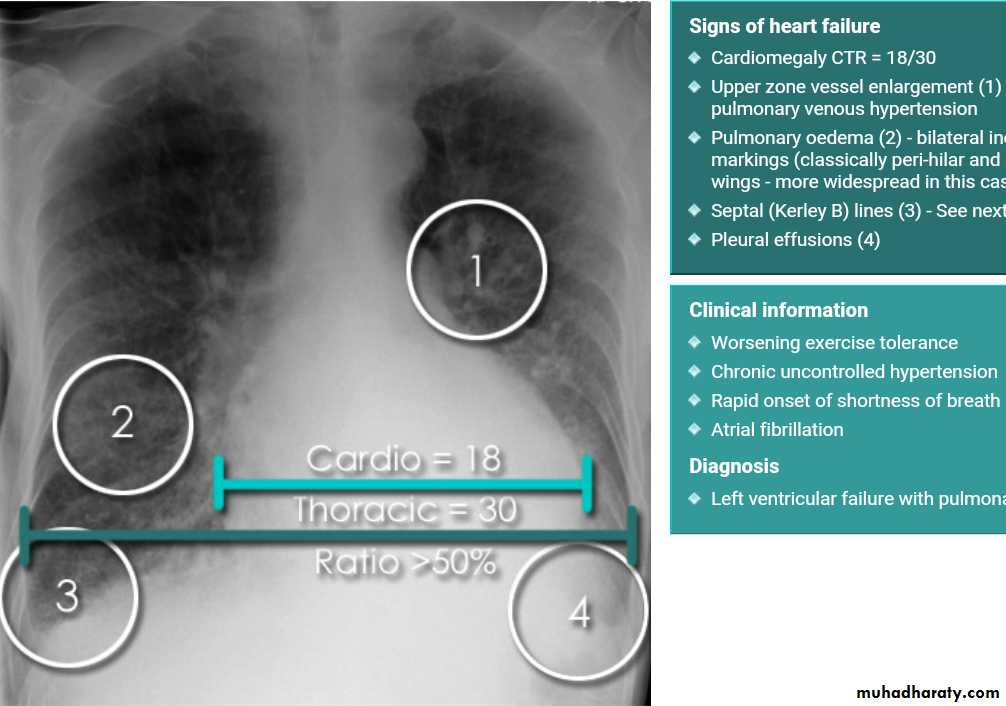

Cardiothoracic ratio (CTR) = Cardiac Width : Thoracic Width

A CTR of greater than 1:2 (50%) is considered abnormal. This however, assumes the projection is Posterior-Anterior (PA), and that cardiac size is not exaggerated by factors such as patient rotation or an incomplete breath in .

The cardiothoracic ratio aids in the detection of cardiomegaly, or more broadly, enlargement of the cardiac silhouette. .

Enlargement of the cardiac silhouette on chest x-ray can be due to a number of causes :

cardiomegaly (most common cause by far)pericardial effusion

anterior mediastinal massprominent epicardial fat pad

With left sided congestive cardiac failure, the features are that of pulmonary edema which includes:

central pulmonary venous congestion ( prominent hilum )

cephalization of pulmonary veins ( upper lobe pulmonary venous diversion )

pulmonary interstitial edema

pulmonary alveolar edema

Cardiomegaly

Pleural effusion